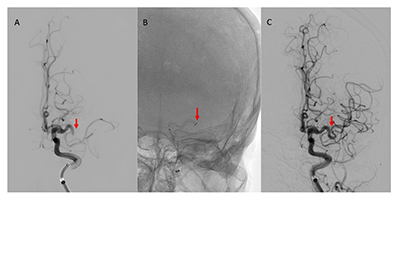

• Hemophilic pseudotumor of the skull: A rare presentation in a young child

Law Zhi Hou, M.D., Barbara Li Lian Kuok, Mrad., Normawati Mat Said, M.D.

230-239